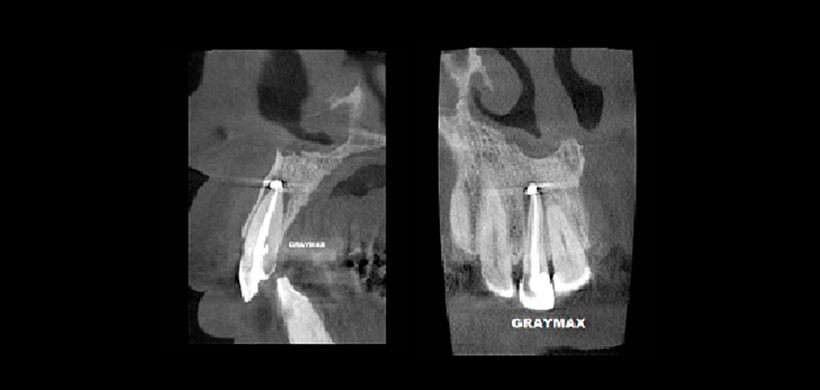

Fig 1. Tomografía computarizada de haz cónico, vista sagital y coronal. Se muestra una lesión apical compatible con una periodontitis apical DE LA PIEZA 1.1.

Fig 2. Tomografía computarizada de haz cónico, vista sagital y coronal. Se muestra la obturación de conducto y la extravasación de material hacia la lesión.